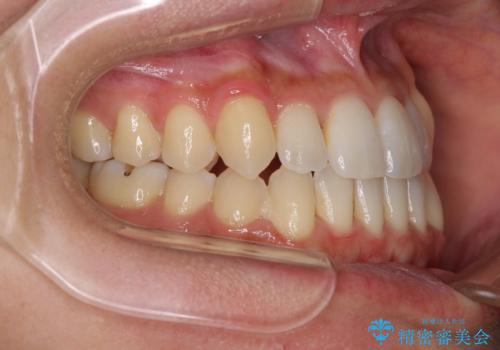

前歯のデコボコ インビザラインによる矯正治療

- 上下前歯の叢生と奥歯の反対咬合を気にして来院された患者様です。

インビザラインを用い、下顎はIPR(歯と歯の間を削る)と歯列全体を後方に移動させ、上顎は側方に拡大させることで歯列を改善していくこととしました。

骨格的に下顎が左側前方にずれているため、上下正中のズレや左右奥歯の咬み合わせを理想的な状態とすることは困難でした。